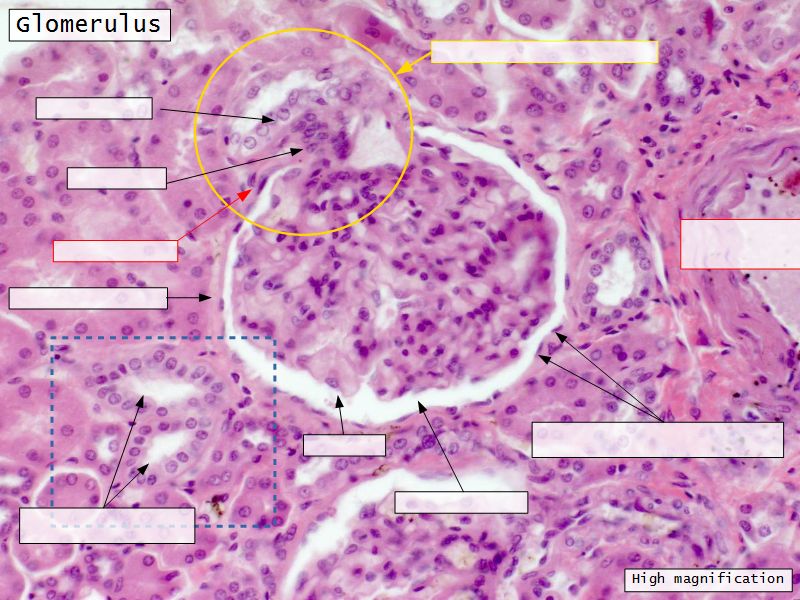

Renal corpuscle

- Tuft of capillaries

- grow into

- Blind end of nephron

- Several layers of epithelium

- Two sides

- Vascular pole

- Tubular pole

Blood flow

- Efferent arteriole

- Smooth muscle in media

- Capillaries

- Fenestrated

- Afferent arteriole

- Smooth muscle in media

Epithelium layers

- Capillary endothelium

- Visceral layer of epithelium

- Podocytes

- Resting on glomerular basement membrane

- Capsular space

- Parietal layer of epithelium

- Simple squamous epithelium

Juxtaglomerular complex